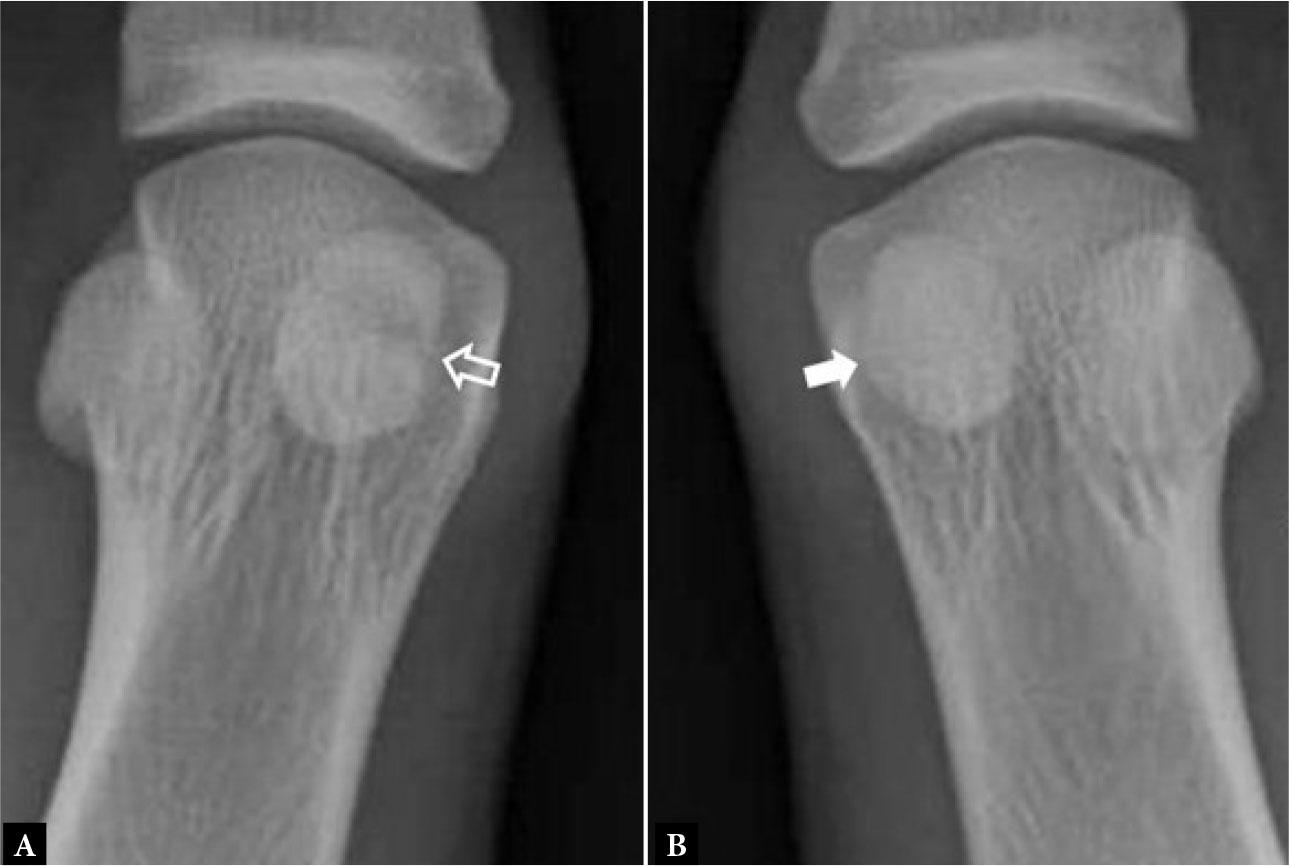

Sesamoid pathology

Sesamoid pathology is quite common and includes osteoarthritis of the sesamoid-first metatarsophalangeal (MTP) articulation, traumatic sesamoid bone fracture, and sesamoid bone stress fracture and sesamoid bone inflammation, known as sesamoiditis, which may be secondary to either stress reaction or osteonecrosis(4). Osteoarthritis between the sesamoid and the undersurface of the first metatarsal head articulation is usually assessed radiographically. Sesamoid fracture is also evaluated by radiography and should be distinguished from a bipartite sesamoid bone (Fig. 3). In bipartite sesamoid, the summated size of both sesamoid components is greater than the expected size of the sesamoid bone. Also, the opposing bone edges are smooth and corticated, with a transversely orientated partition, as opposed to the often irregular, obliquely orientated margins of a sesamoid fracture (Fig. 4). Sesamoiditis is seen on MRI examination as diffuse edema of the affected sesamoid bone.

16-year-old female with recent pain plantar aspect 1st MTP joint following a gymnastics tournament. A. Dorsoplantar radiograph of 1st MTP joint shows irregular transverse fracture medial sesamoid bone (open arrow). B. For comparison, on a dorsoplantar radiograph of the contralateral, asymptomatic 1st MTP joint, the medial sesamoid bone is normal (arrow)